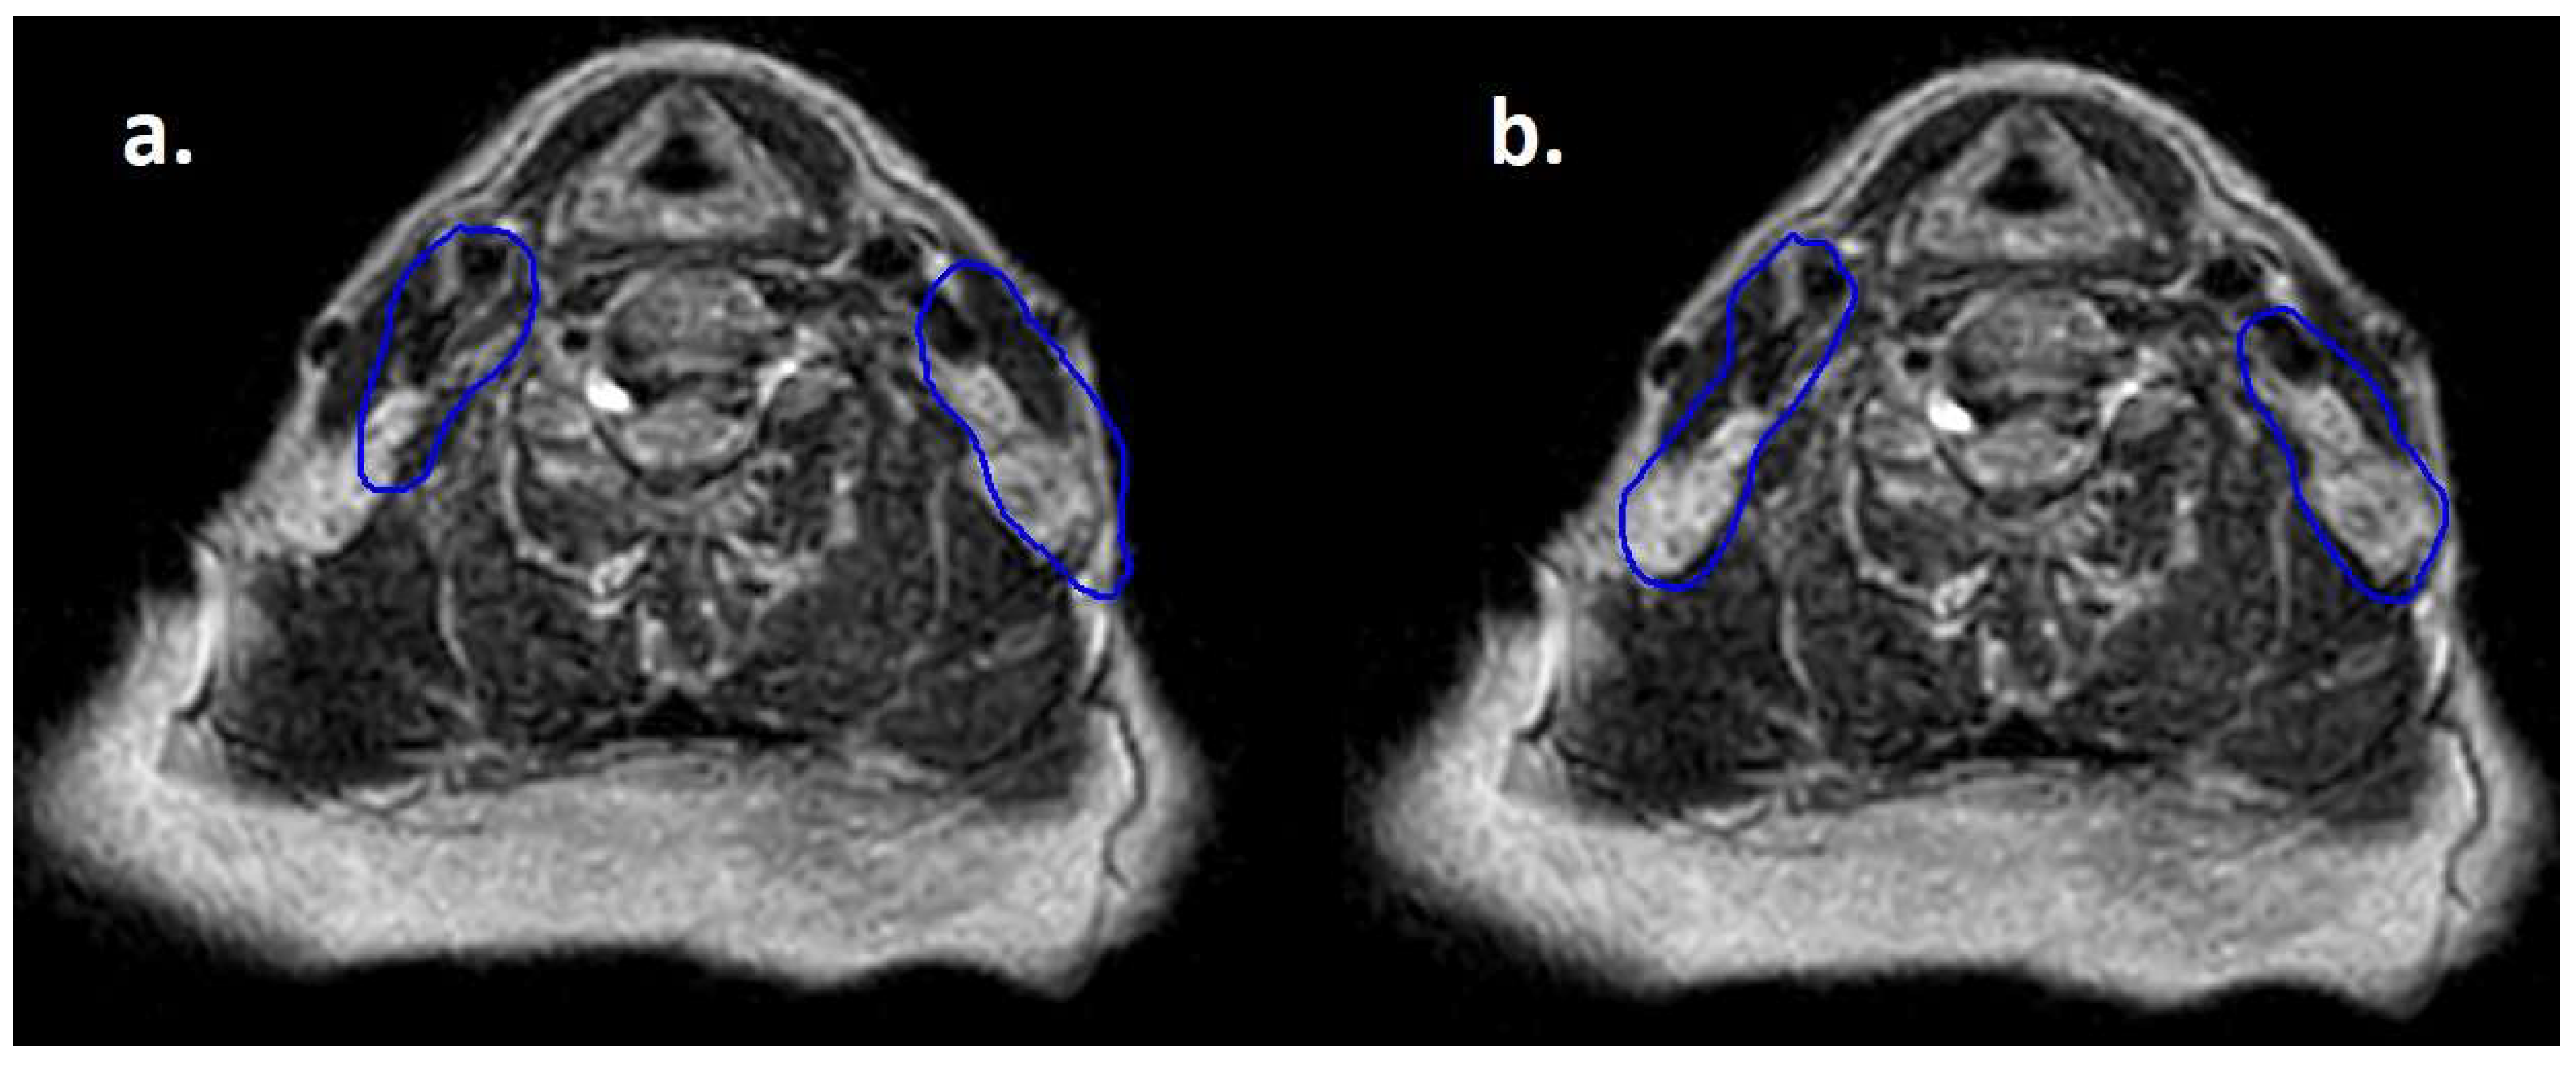

Figure 2.

Daily MRI at the sixth fraction of radiotherapy of the patient that received bridging therapy before CAR-T with a dose of 3 Gy per fraction. In (a) contours rigidly propagated from simulation MRI; in (b) contours deformably registered, manually edited and used for treatment delivery.

Moreover, lymphomas are radiosensitive neoplasms that tend to respond early during the course of radiotherapy, often leading to a substantial volume reduction (as exemplified in Figure 1). While “conventional” CT-based image-guided radiotherapy (IGRT) might allow for the detection of major volumetric variations, MRI-based IGRT enables the identification of even slight differences due to improved soft tissue contrast. Moreover, in our cohort every patient was treated using a daily adapt-to-shape workflow, in which contours of the target volumes and OARs are manually edited for each fraction on the basis of daily MR imaging (as exemplified in Figure 2) and the treatment plan is extensively recalculated. The possibility to adapt contours and the treatment plan on the basis of daily MRI scans could improve dose distribution and guarantee optimal target coverage compared with conventional RT, while sparing surrounding organs at risk [21,22]. This should conceptually result in reduced treatment-related toxicity; nonetheless, clinical data to confirm this hypothesis are awaited (also due to the novelty of this technology).